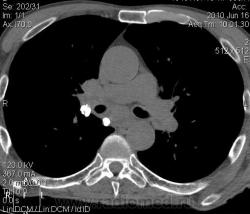

Мужчина 69 лет, с последствием ОНМК находился в доме-интернате для инвалидов. В анамнезе пневмония справа и исходом в пневмосклероз. ФЛГ не проходил 1.5 года. Анализы: СОЭ 20 мм/ч, остальное - без особенностей. Поступил в неврологическое отделение с диагнозом: повторное ОНМК. Невролог заподозрил метастазы головного мозга, направил на рентгенографию легких. После выявленых изменений в правом легком, пациент направлен на КТ головного мозга и грудной полости. От контрастирования и бронхоскопии категорически отказался.

По поводу подозрения на туберкулез пациента в прошлом нодократно проверяли, исключили. ФЛГ архива у меня нет. Все только со слов пациента. Кальцинаты в корне массивные. Трудно сказать, откуда опухоль (если это не конгломерат лимфоузлов!) плотностью 35 ед.Н - то ли из вехнедолевого бронха, который имеет культю 0.4 см и заканчивается выпуклым контуром, но при этом сохраняется воздушность почти всей доли; то ли периферический с центром в прикорневой зоне и вторичным прорастанием ВДБ. К сожалению забыла про снимок легких, на днях выставлю. Я первоначально считала периферический (верхушка, на фоне пневмосклероза) с мтс средостения. По плотности на верхушке узелок 5 ед.Н, только поэтому засомневалась, где же первичный. Лимфоузлы средостения множественные, до 2 см. Кроме того, на верхней стенке правого главного бронха есть мелкое образование такой же 35 е.Н плотности, то ли аденома, то ли прорастает... Без бронхоскопии - только гадать

А тут нечего гадать - данную демонстрацию можно поместить в учебник: узловое образование, с бугристыми, лучистыми контурами, связаное с плеврой, "дорожкой" к корню, перифокальной инфильтрацией. Корень расширен полицикличен за счет конгломерата увеличеных бронхопульмональных, трахеобронхиальных и бифуркационных л/узлов, значительно сдавливающих в/долевой бронх, с нарушением вентиляции в/доли.

Центральный рак ВДБ справа с мтс в л/узлы паратрахеальные нижние, верхние справа, БФ. МТС в головной мозг. А про печень мало сканов

Мне кажется в 6 сегменте печени мтс + еще мтс поражение левого надпочечника вероятнее всего. Мтс в нижние паратрахеальные (с обеих сторон)+бифуркационные л/у. Поражения верхних паратрахеальных не вижу (на коронарах), аксиалы - не показыны сканы выше верхнего края дуги аорты, так что я бы не говорил про поражение верхних медиастинальных лимфоузлов (хотя тут это уже не принципиально) + мтс в головной мозг. А так - центральный рак правого легкого.